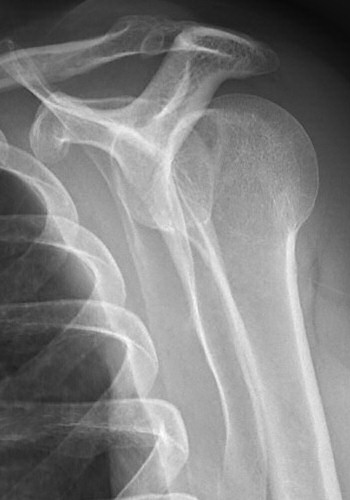

Främre luxation

Efter reponering